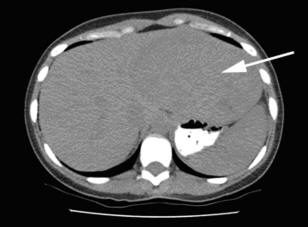

Metastatic retroperitoneal epithelioid angiomyolipoma Chakshu Gupta, Ashok K Malani, retroperitoneum, liver and bone. Figure 3 Abdominal ultrasound (A) and CT scan (B,C) demonstrate liver mass. A ... Return Doc